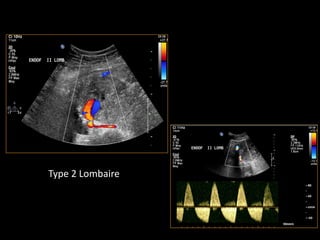

Type 2 Lombaire

ENDOFUITE TYPE 2

TYPE 2TYPE 2

ReperfusionReperfusion parpar

circulation rcirculation réétrogradetrograde

(branche(s) de l(branche(s) de l’’aorteaorte

native)native)

ArtArtèère lombaire,re lombaire,

mméésentsentéérique infrique inféérieure,rieure,

iliaque interneiliaque interne